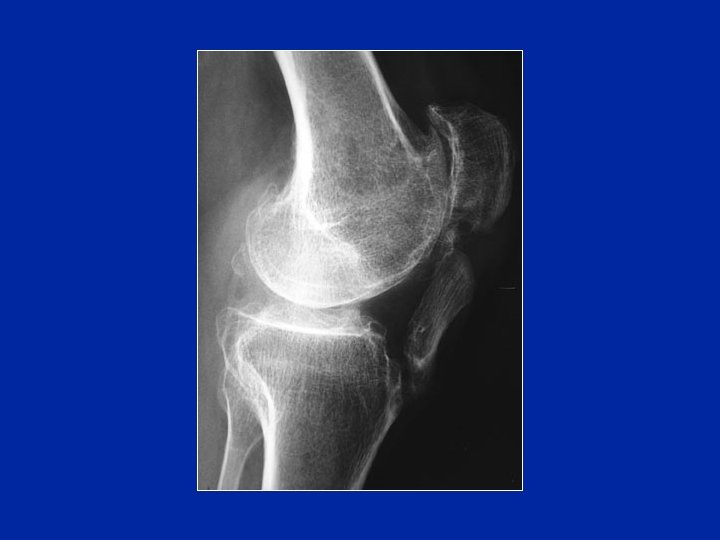

Rupturas antiguas Rótula alta e insuficiente para la fuerza de extensión de la rodilla

Secuelas

Secuelas Calcificaciones sub-rotulianas: aspecto de rótula doble